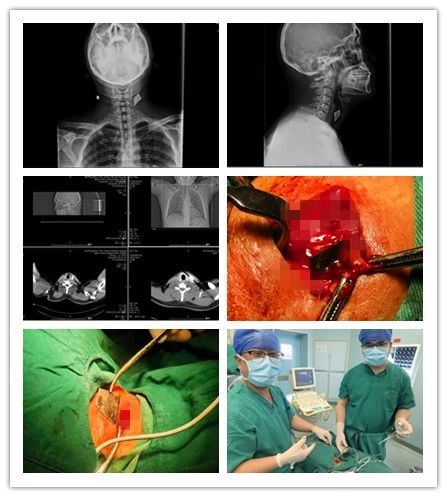

近日,一位“美工刀”刀刺傷的患者來我院乳腺甲狀腺外科就診,頸部正側(cè)位拍片顯示“美工刀片”深入頸深部,嚴重危及生命。乳腺甲狀腺外科團隊以十分鐘的“小手術(shù)”成功為患者解除危機,患者現(xiàn)已痊愈出院。

患者,男,35歲,3個月前頸部被銳器刺傷,傷后出血量約50ml,伴有疼痛,不伴有麻木,呼吸正常,于外院行清創(chuàng)縫合手術(shù),術(shù)后切口反復(fù)感染,并伴有頸部及左側(cè)上肢放射性疼痛,后于我院復(fù)查頸部正側(cè)位片示左側(cè)頸前不規(guī)則致密影,門診以“左頸部異物”收入院。

乳腺甲狀腺外科王思雷和楊汶士主治醫(yī)師接診后,追問患者病史并仔細檢查,確認患者皮膚淺層不存在異物,認為異物存在于頸深部,且異物為銳器“美工刀片”,有傷及頸部大血管及氣管、食管可能,隨時危機生命,建議手術(shù)取出。但異物位置深,緊鄰頸部大血管、氣管、食管,存在較大手術(shù)難度和風(fēng)險??浦魅卫罘搴屯跛祭?、楊汶士主治醫(yī)師進行充分術(shù)前討論后,制定了周密的手術(shù)方案,在彩超及C臂機引導(dǎo)下,精確定位,為患者施行頸部異物取出術(shù)+清創(chuàng)縫合術(shù)。術(shù)中發(fā)現(xiàn)異物為銳器“美工刀片”,刀刃鋒利,位置深達頸椎前側(cè),緊鄰頸部大血管及氣管、食管,差之毫厘便可能造成血管破裂致大出血。兩位醫(yī)師憑借嫻熟的技術(shù),小心翼翼探查,僅用十分鐘便成功取出異物。